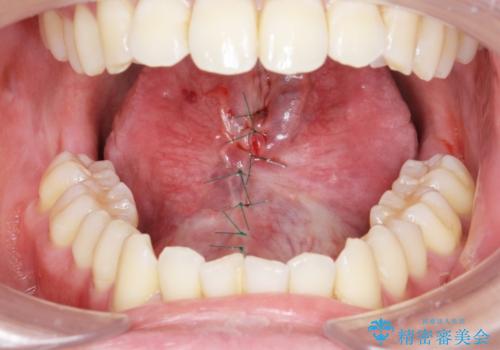

- 舌の動きが舌小帯により制限され、滑舌の改善を求めて来院されました。

形成手術を行うことで、舌の動きをより自由に行うことが期待できます。

発音しづらかった、サ行・タ行・ナ行の音が改善され喜んでいただくことができました。